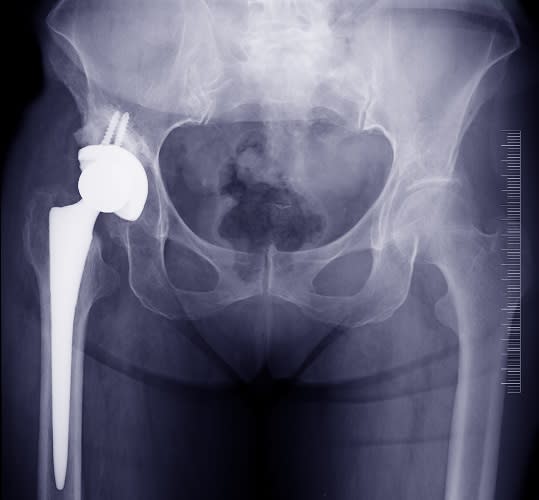

Son objectif est de remplacer la hanche à l’aide d’un pivot (la tige fémorale) implanté dans le fût fémoral et sur lequel est placée une tête qui va s’articuler avec une seconde partie placée dans le bassin (le cotyle). Le moteur articulaire que constituent les muscles n’est pas modifié et dépend donc de l’état préalable à l’intervention. Il existe de nombreux modèles de prothèse totale de hanche comme cependant on peut les définir par trois paramètres principaux :

- La fixation. Peut être obtenue avec du ciment ou par un contact étroit entre la prothèse et l’os avec un accrochage biologique. Les indications sont différentes et dépendent de l’état osseux.

- La surface de frottement entre la tête fémorale et le cotyle. Elle peut associer une tête en métal ou en céramique avec un insert cotyloïdien en plastique de synthèse ou associer une tête céramique à un insert du même matériau. Chaque couple a ses avantages et inconvénients.

- Le concept de la prothèse qui peut être dit à double mobilité. Ainsi le risque de luxation est diminué. Cependant ces prothèses ne peuvent être fabriquées qu’en céramique.